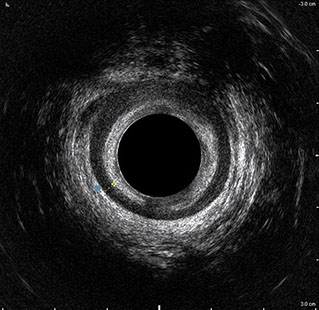

L’ecografia transanale permette di distinguere la sottomucosa che riveste il canale anale, lo sfintere anale interno, e lo sfintere anale esterno.